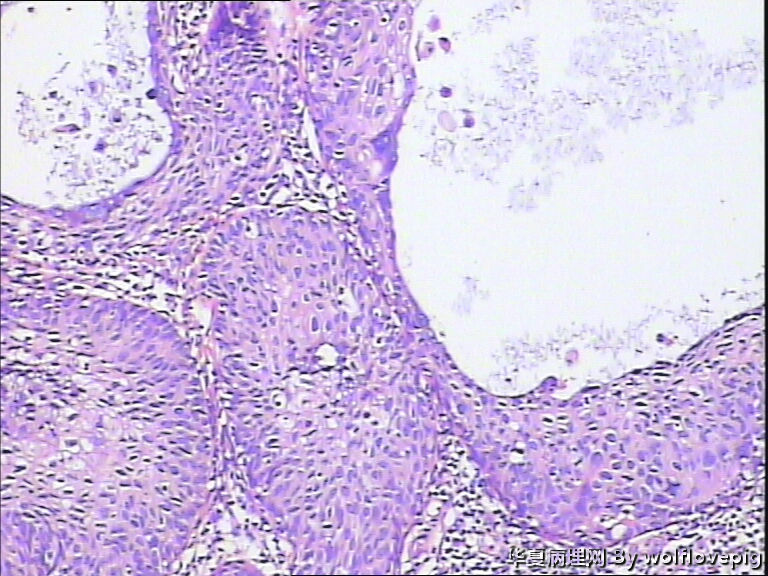

求助,宫颈!

37y

CIN3累腺

CINIII累及腺体

同意CINIII累及腺体

CIN-II 累及腺体。我看不够原位癌。学习了!

CIN2-3,累腺